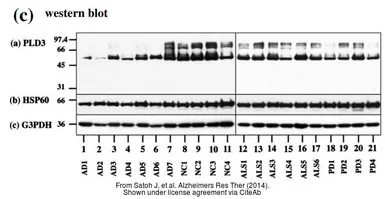

The data was published in the 2014 in Alzheimers Res Ther. PMID: 25478031